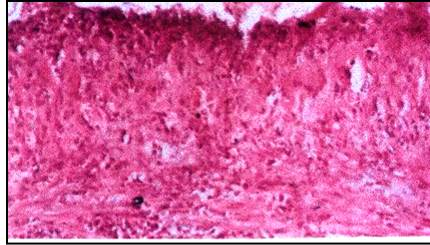

Histological examination of the surface mucosa of the stomach fundus of the rats of the control group displayed a normal mucosa lined with normal epithelial cells regularly, Fig. (3). As shown in this figure, the normal epithelial cells are tall columnar and contain an oval nuclei. The fundus glands are occupied all the thickness of the mucosa laminapropria and are arranged in perpendicular manner to surface epithelium. Mucous neck cell, cuboidal with flat nuclei, are observed very near to the epithelial cells.

The last layer of the mucosa is the muscularis mucosa. While, the histological examination of the gastric mucosa of the stomach fundus of the rats of the group 1 (administrated intact FP) showed marked destruction with complete disappearance of mucosal surface epithelium indicating to marked ulceration effects, Fig. (4). On the other side, fig. (5) displayed nearly a typical normal mucosa upon investigation of the stomach of the rats of the group 2 (administrated F-1). While, fig. (6) displayed a minor ulceration in the lining epithelial of the fundus mucosa cells of the rats of the group 3 (administrated F-1*). These results reflected that FP matrix formulations prepared by the alternative technique could be highly reduced the ulcerogenic effects rather than FP matrix formulations prepared by the traditional wet granulation.

Fig. 3: Gastric mucosa of a rat control group given suspension of 1% gum acacia